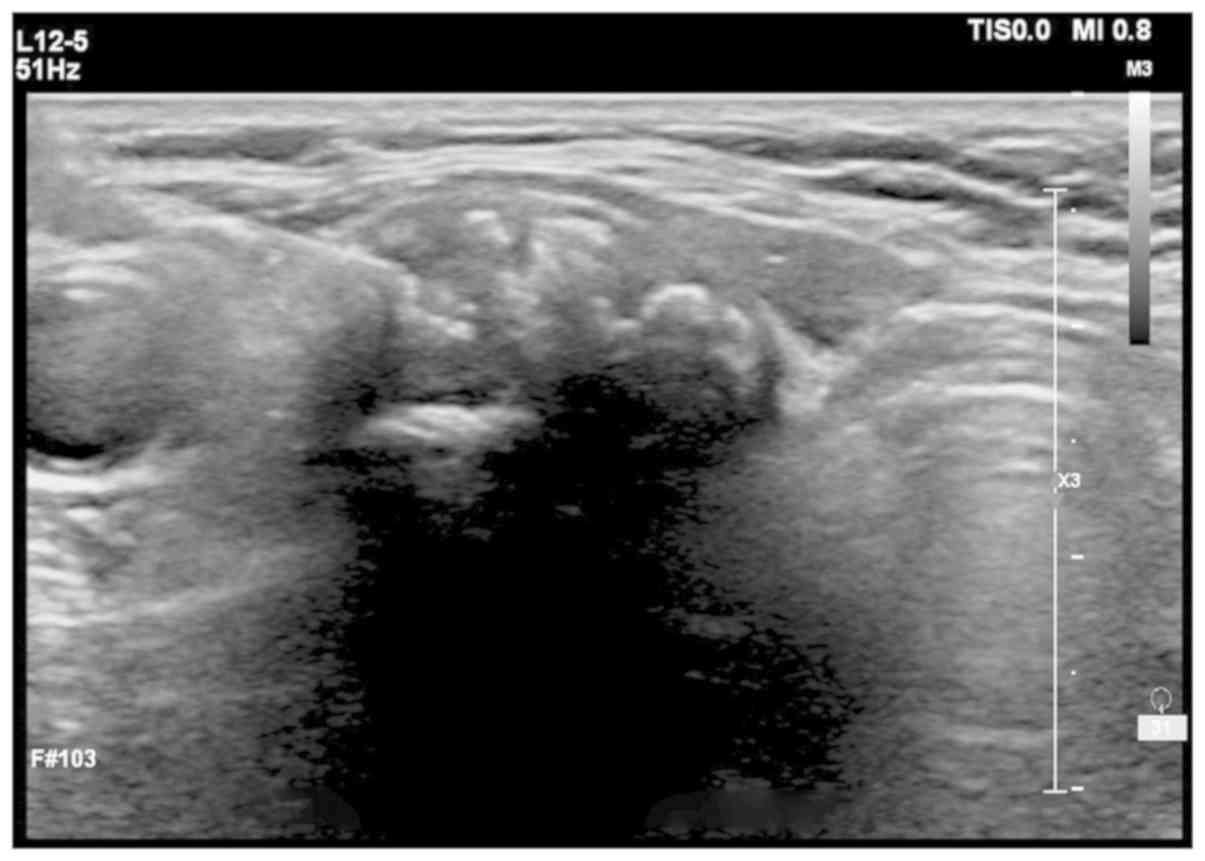

Ultrasonography Performed On 61 Year Old Female With Medullary Thyroid Download Scientific Diagram

Micro Medullary Thyroid Carcinoma A Diagnosis Not To Be Missed In A Patient With Neck Cavernous Hemangioma Aace Clinical Case Reports